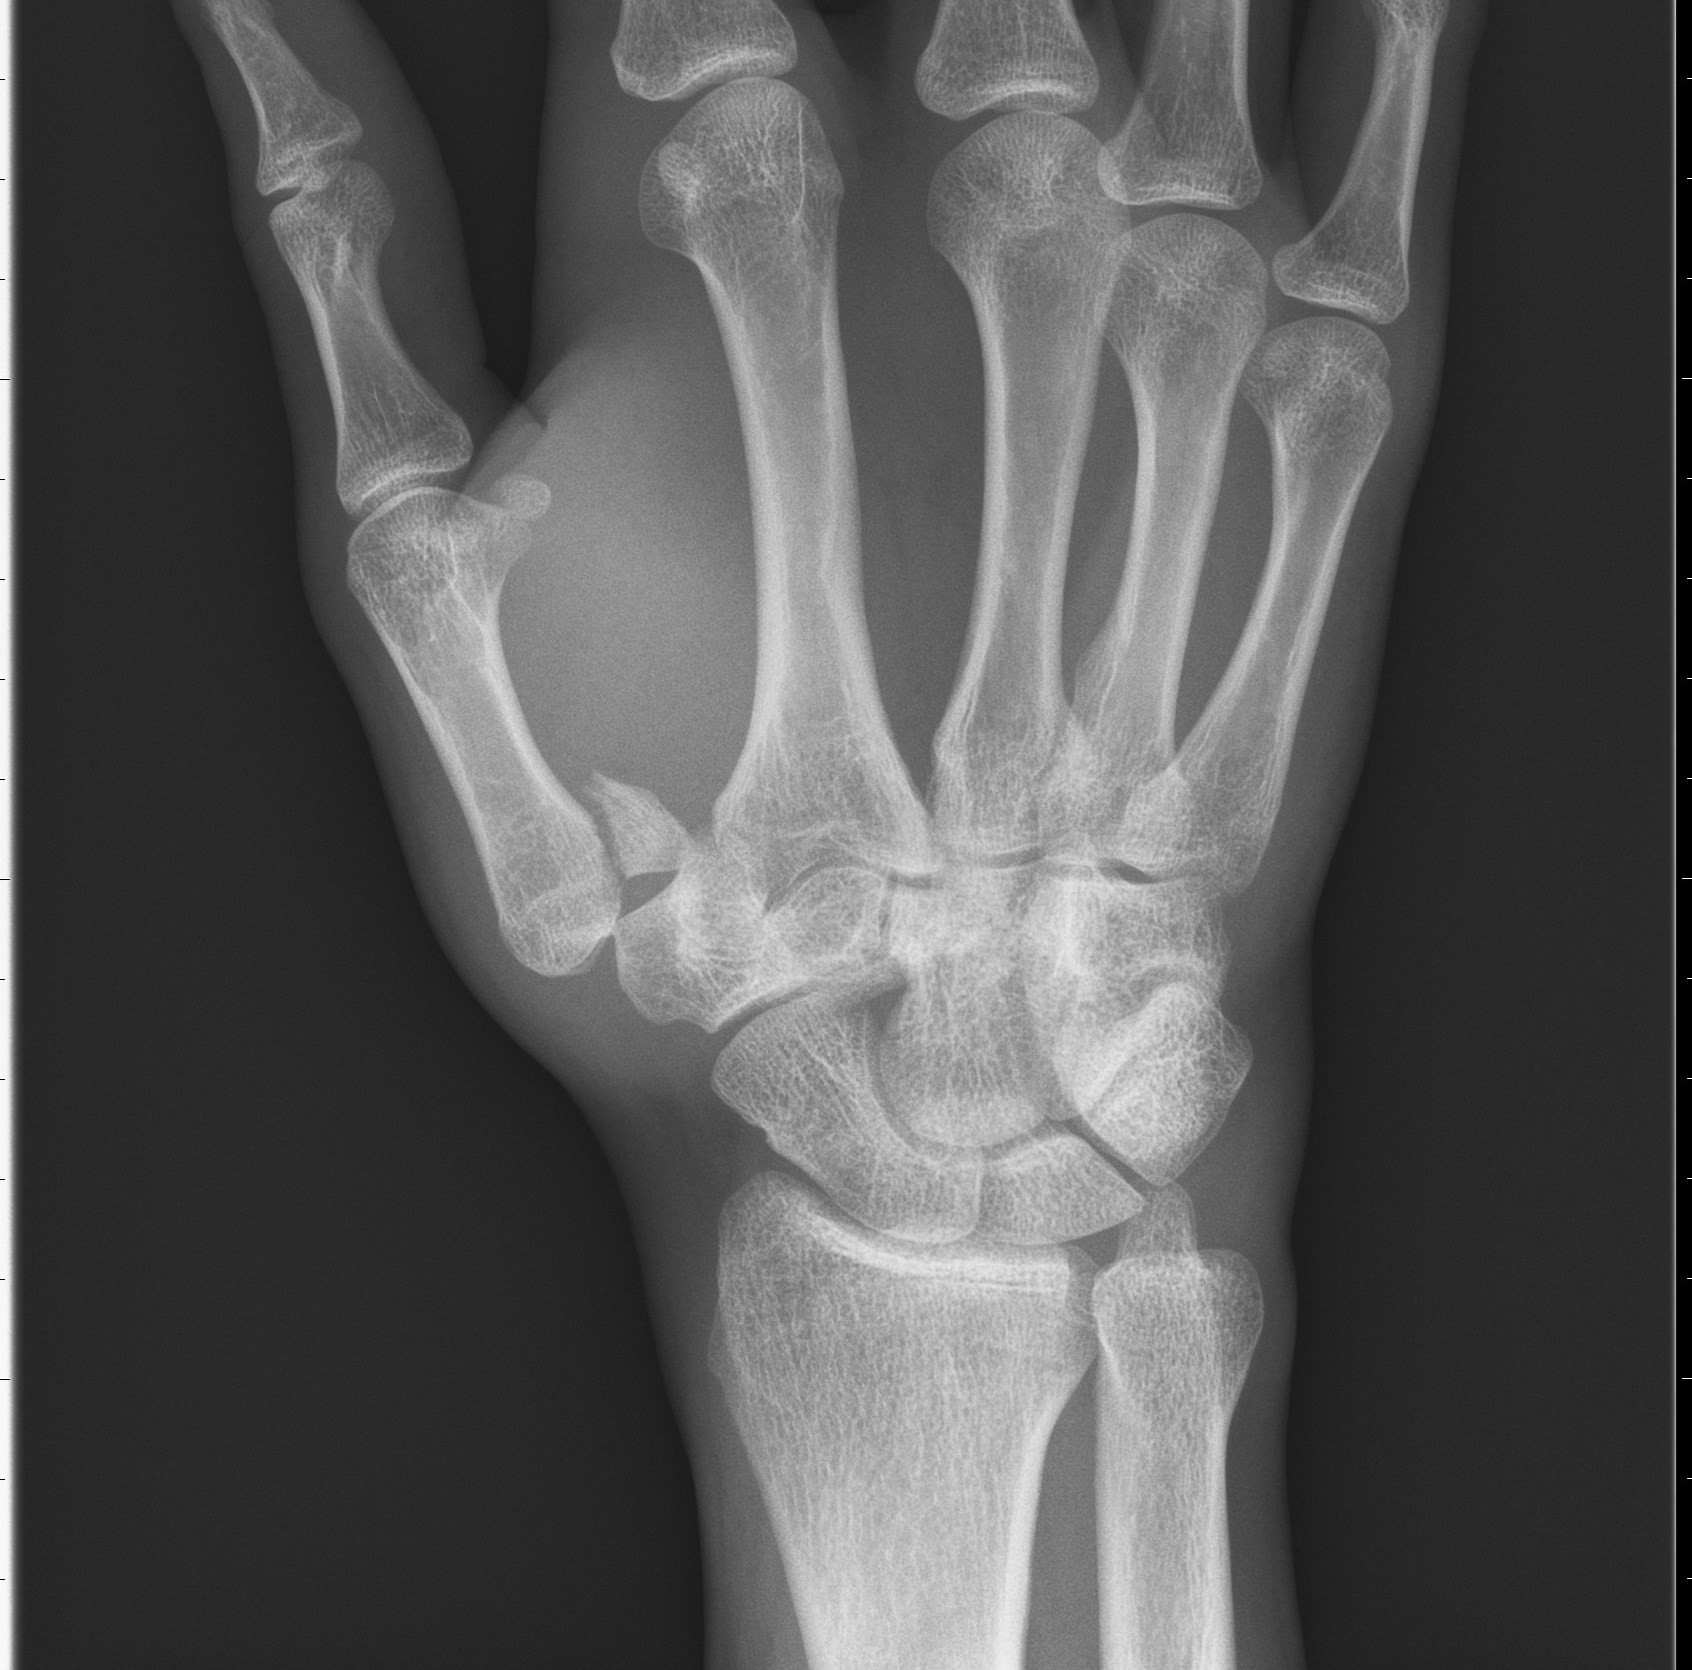

Grundläggande behandling av hand- och handledsfrakturer skiljer sig egentligen inte från annan frakturbehandling; reposition av felställningen, bibehållande av repositionsläget via intern eller extern fixation och immobilisering tills frakturen är övningsstabil. Detta är grundprinciper som gäller även inom handkirurgin.

En skillnad är emellertid att handens småleder är känsliga för kvarvarande frakturhak efter intraartikulära frakturer och att handen är särskilt känslig för långvarig immobilisering. Båda dessa faktorer medför att operativ behandling tillämpas oftare för handfrakturer än för övriga frakturer.

Indikationen för operation av en fingerfraktur är ofta att omvandla en instabil fraktur till en stabil, allt i avsikt att förkorta immobiliseringstiden och starta aktiv rörelseträning så tidigt som möjligt.

Handen bör alltid immobiliseras i funktionsställning, dvs handleden rak eller lätt extenderad, MCP-lederna kraftigt flekterade (90°), interfalangeallederna raka och tummen palmar abducerad och lätt semiflekterad i MCP-leden. Fingerfrakturer bör ej immobiliseras längre än 3 veckor (över PIP-lederna).

Även om frakturen inte är helt röntgenologiskt läkt, bör rörelseträning ändå sättas igång. Handens funktion prioriteras före frakturens läge och läkning. Radiologisk läkning syns oftast först efter ca 6 veckor, medan frakturen ofta är stabil för obelastad rörelseträning efter 3 veckor.